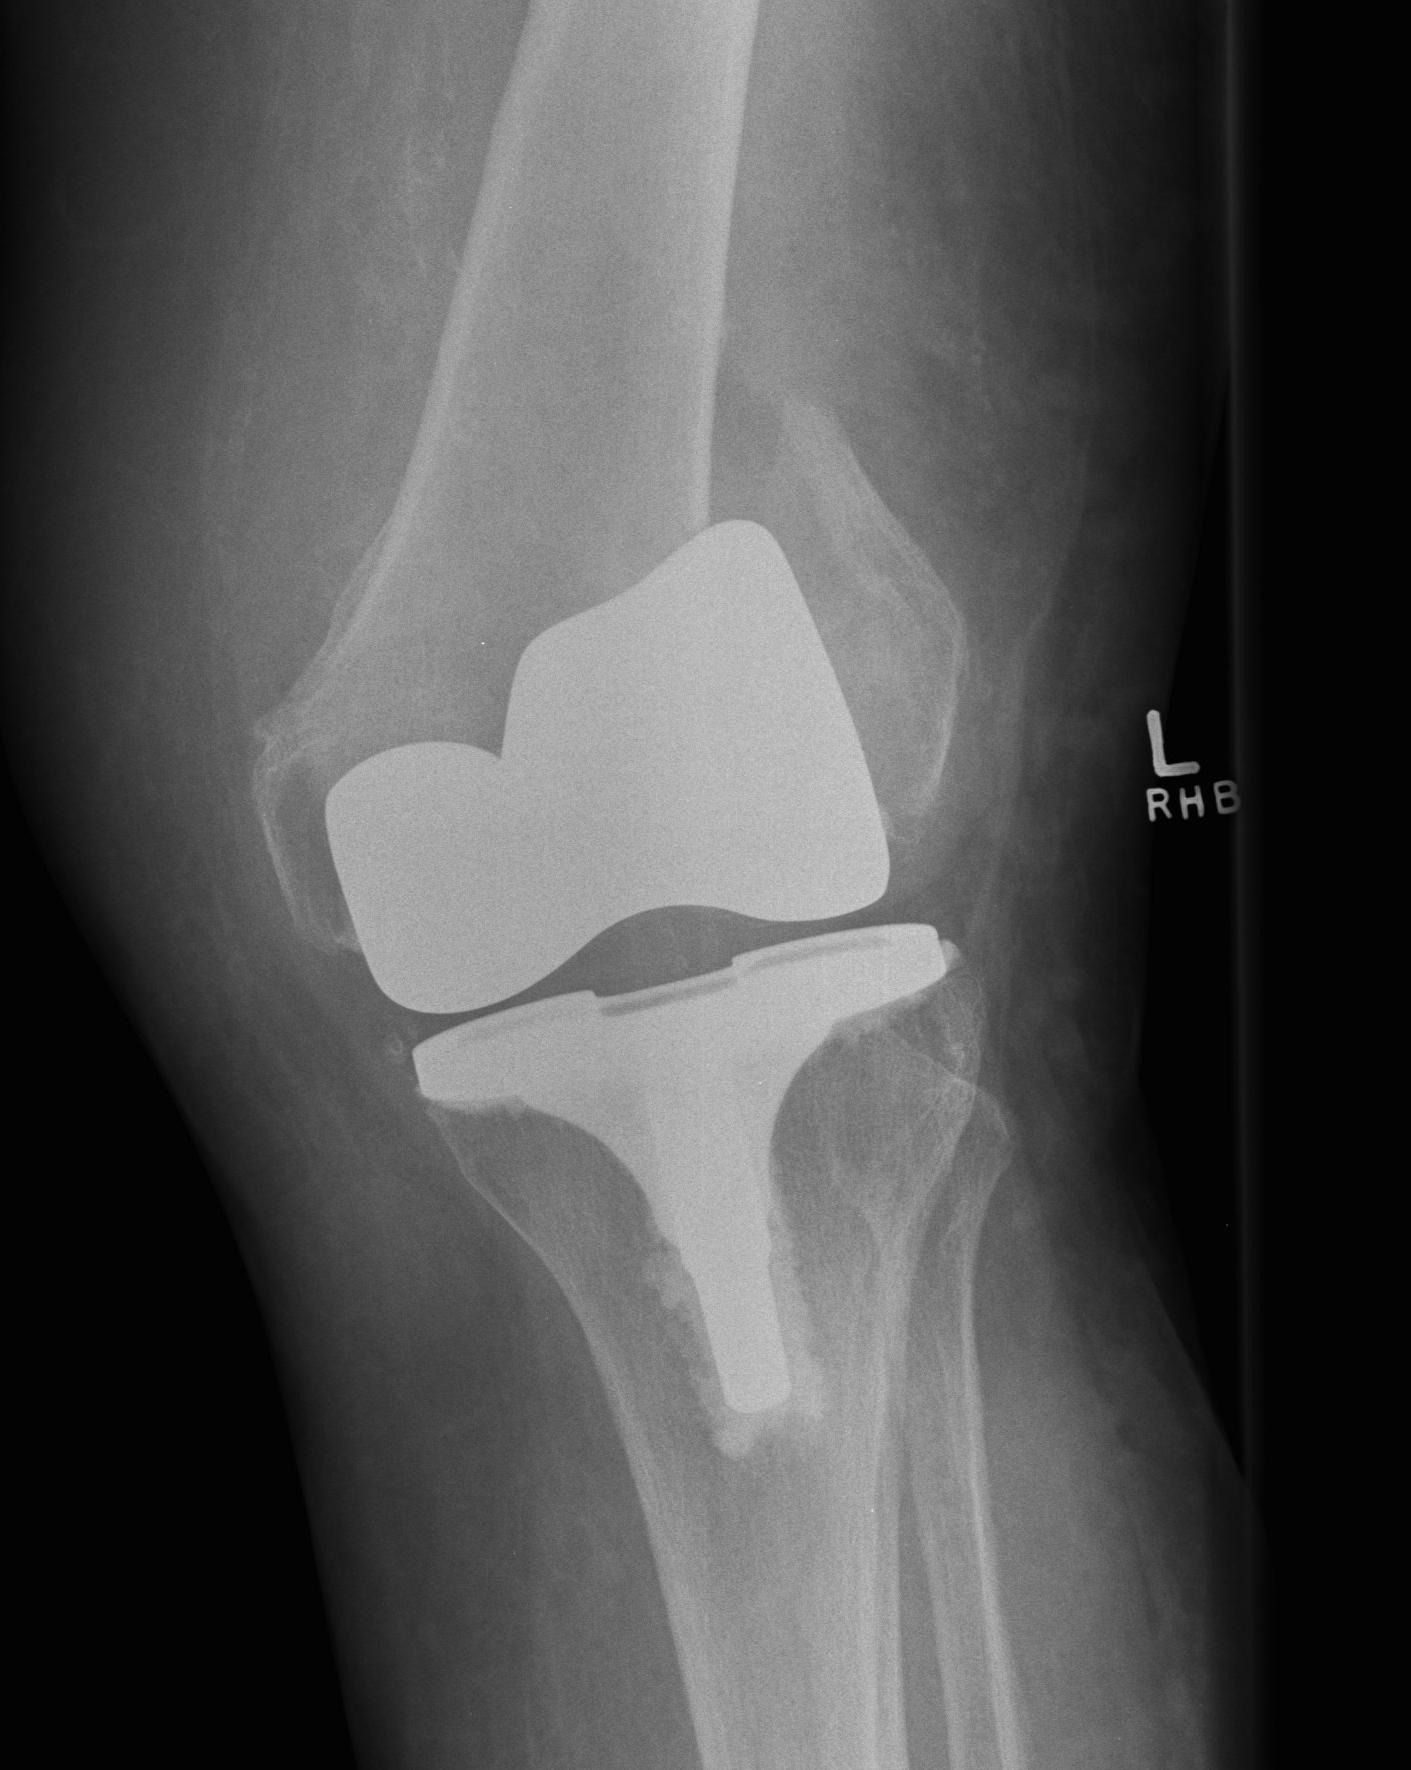

TKR Intraoperative condylar fractureTKR Condylar Fracture Lateral